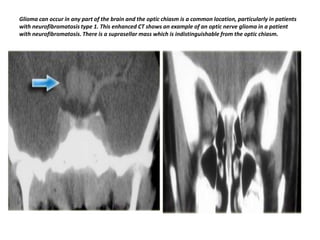

Glioma can occur in any part of the brain and the optic chiasm is a common location, particularly in patients

with neurofibromatosis type 1. This enhanced CT shows an example of an optic nerve glioma in a patient

with neurofibromatosis. There is a suprasellar mass which is indistinguishable from the optic chiasm.